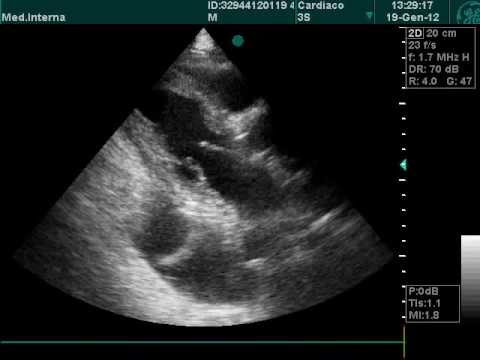

This video shows pleural effusion on both pleural cavities with lung tissue floating in the fluid. Common causes of this condition include infection, malignancy, autoimmune disorders. The fluid seems to be clear, having no internal echoes. Pleural plaques and calcifications may be seen, suggesting history of asbestos exposure. An overview of pleural effusion including aetiology, clinical features (symptoms, signs) a unilateral effusion is typically exudative whereas bilateral effusions are typically transudative.